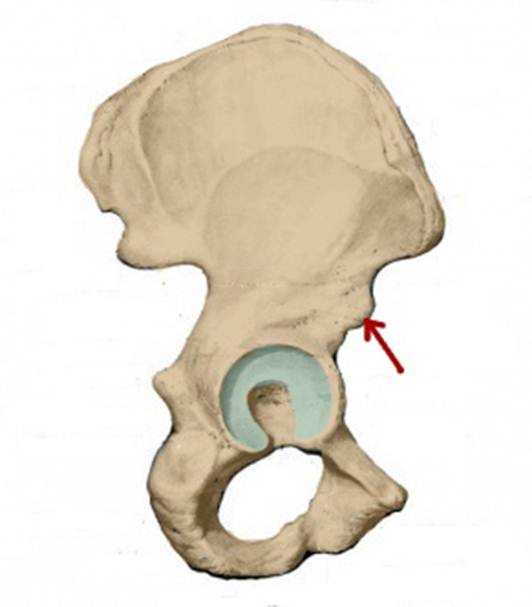

I:

S: Стрелка указывает на os pubis (латинский язык).

I:

S: Стрелка указывает на os ilium (латинский язык).

I:

S: Стрелка указывает на os ischii (латинский язык).

S: Стрелка указывает на facies lunata (латинский язык).

S: Стрелка указывает на spina iliaca anterior inferior

S: Стрелка указывает на spina iliaca anterior superior

S: Стрелка указывает на eminentia iliopubica

I:S: Стрелка указывает на spina iliaca anterior superior